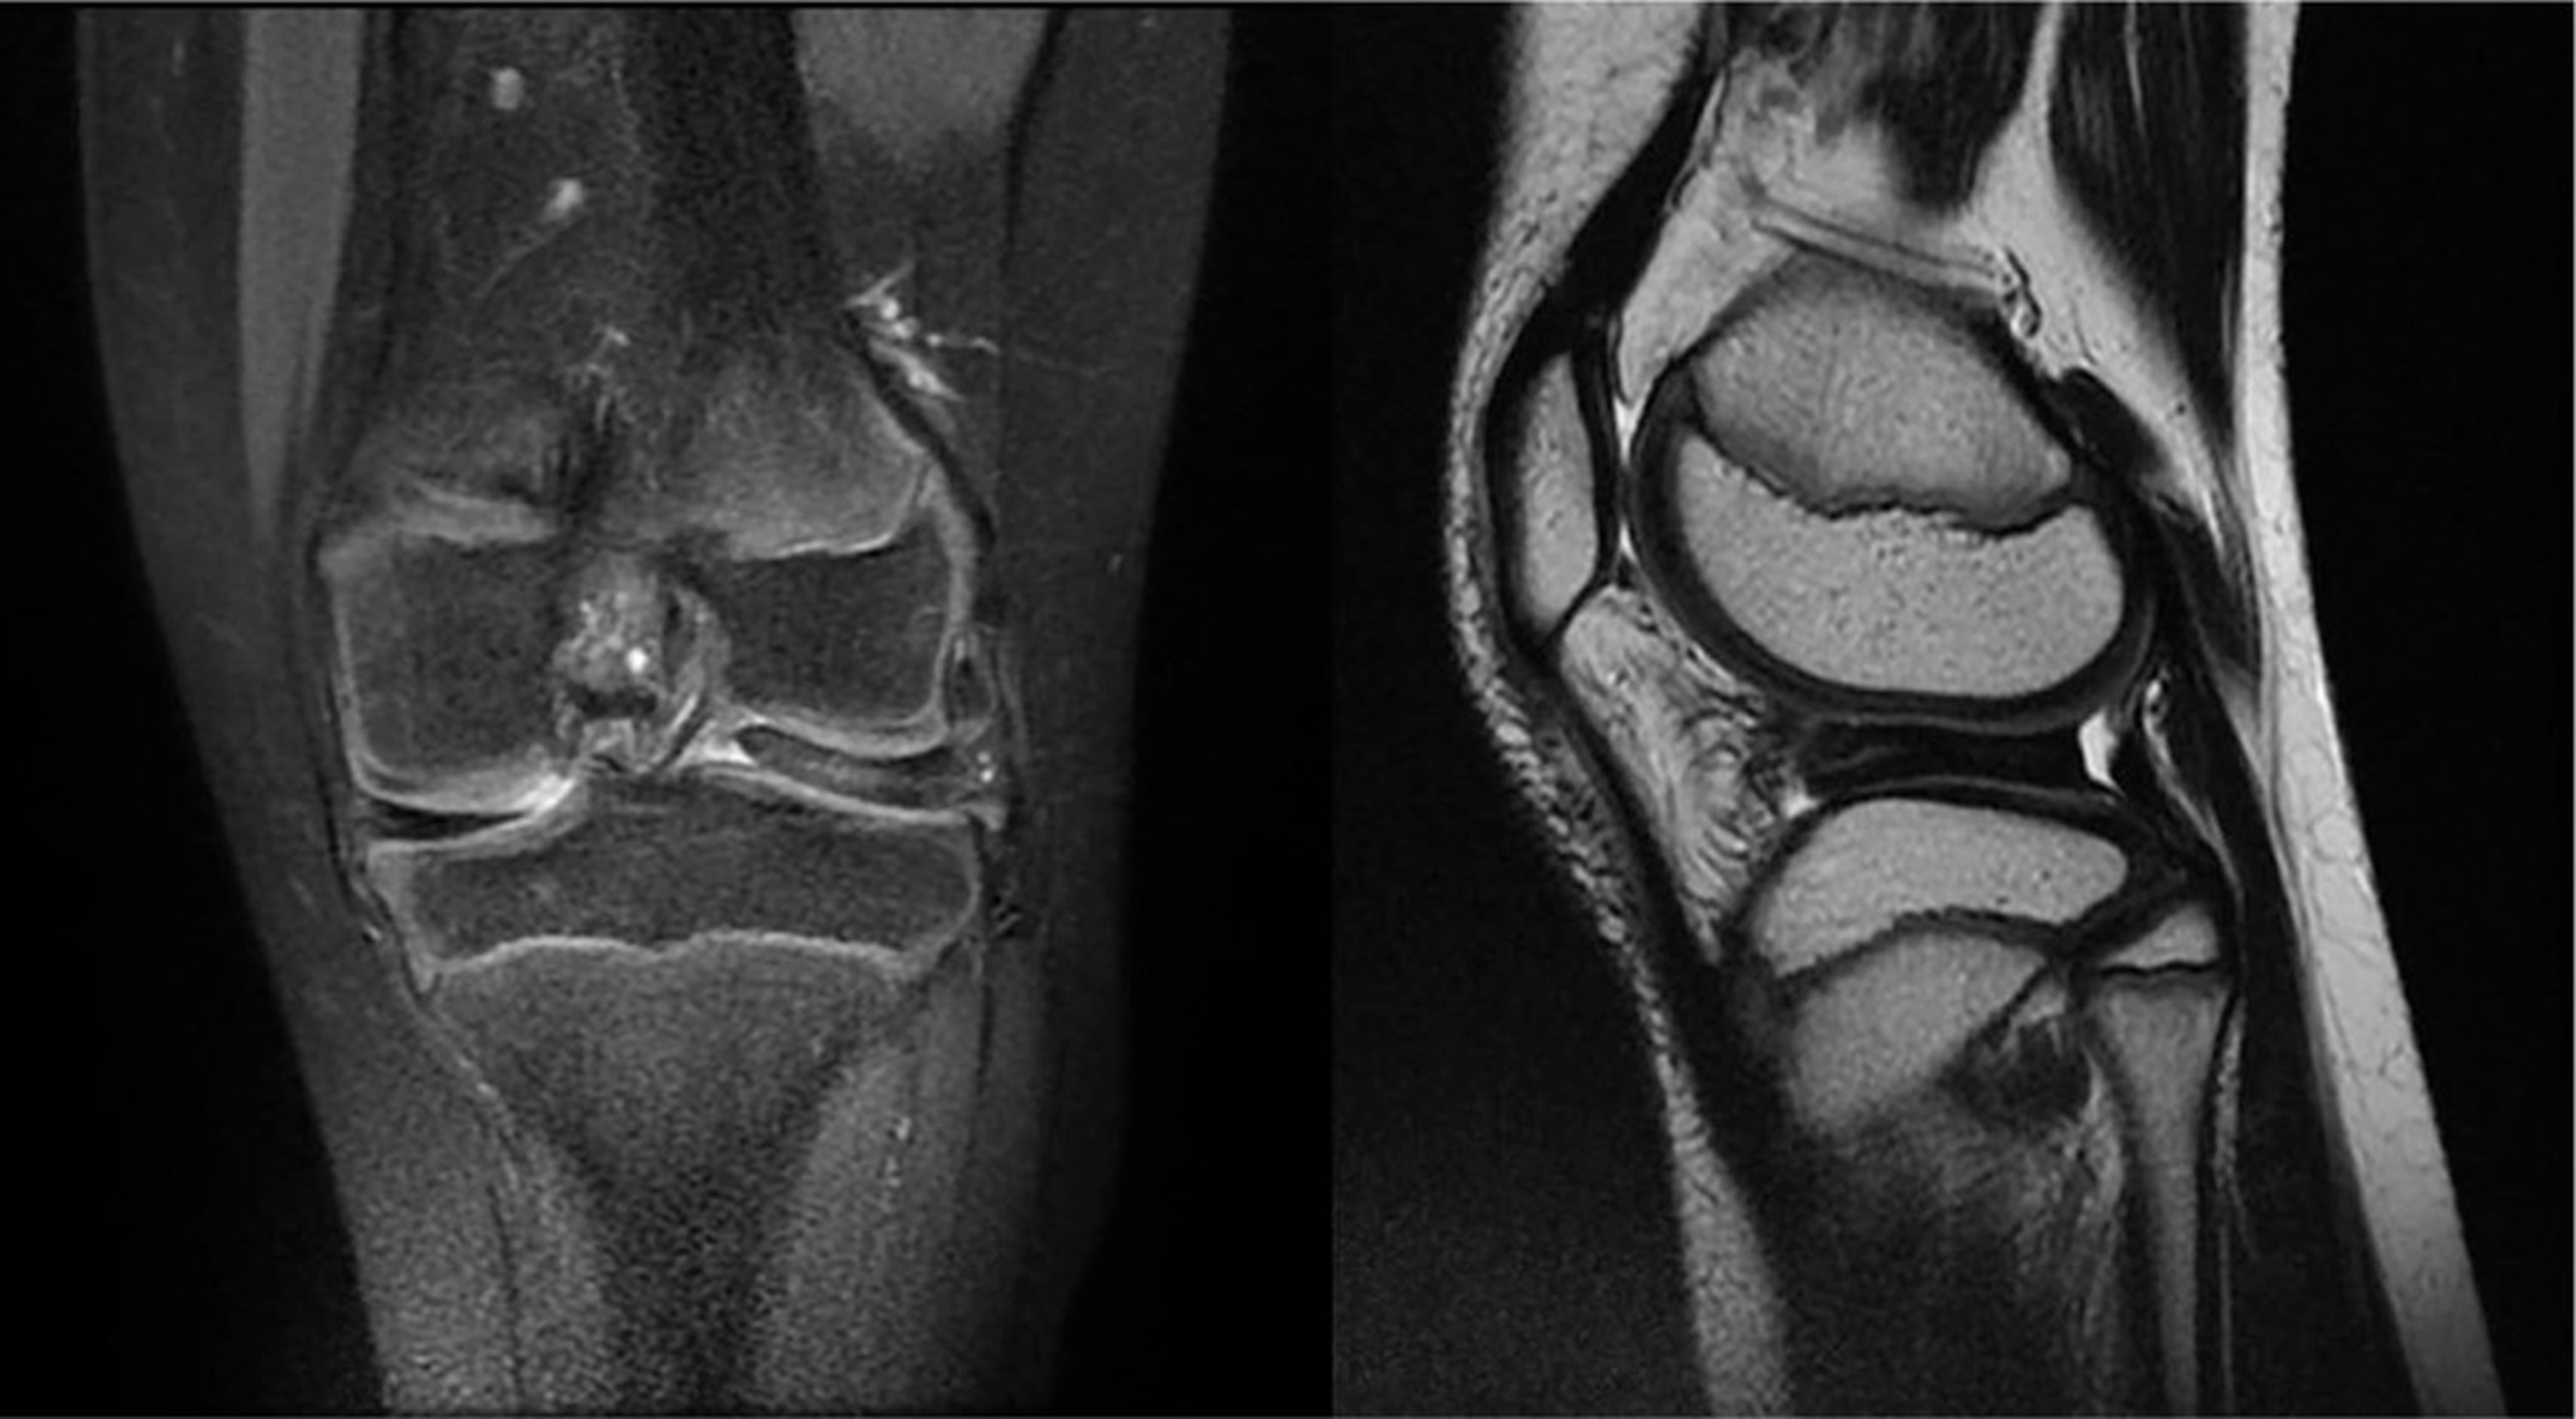

L’esame radiografico può mettere in evidenza segni indiretti della presenza di un menisco discoide, ma l’esame diagnostico di riferimento resta la risonanza magnetica che permette di identificare anche eventuali lesioni a carico del menisco.

ll trattamento chirurgico trova invece indicazione in presenza di una sintomatologia tipica, non responsiva alle terapie conservative. Le opzioni a disposizione vanno dalla saucerizzazione, ossia un rimodellamento del menisco discoide sino ad ottenere una normale morfologia e funzione meniscale, la stabilizzazione periferica associata o meno alla centralizzazione qualora sia presente una problematica di instabilità sino alla riparazione dei diversi pattern lesionali. A prescendere dal tipo di trattamento chirurigico, l’obiettivo è quello di preservare quanto più possibile il tessuto meniscale.

La prognosi è generalmente positva, soprattutto in caso di chirurgia conservativa. Come evidenziato da studi recenti (Erden et al. 2025) la maggior parte degli adolescenti trattati può riprendere l’attività sportiva, anche a livello competitivo. Tuttavia, il ritorno in campo non è l’unico obiettivo da perseguire, ma bisogna considerare le conseguenze a medio e lungo termine e il possibile rischio di recidiva. Infatti, è stata dimostrata una precoce ed accelerata progressione verso l’artrosi in caso di meniscectomia subtotale o totale rispetto alla meniscectomia parziale e alla riparazione meniscale.